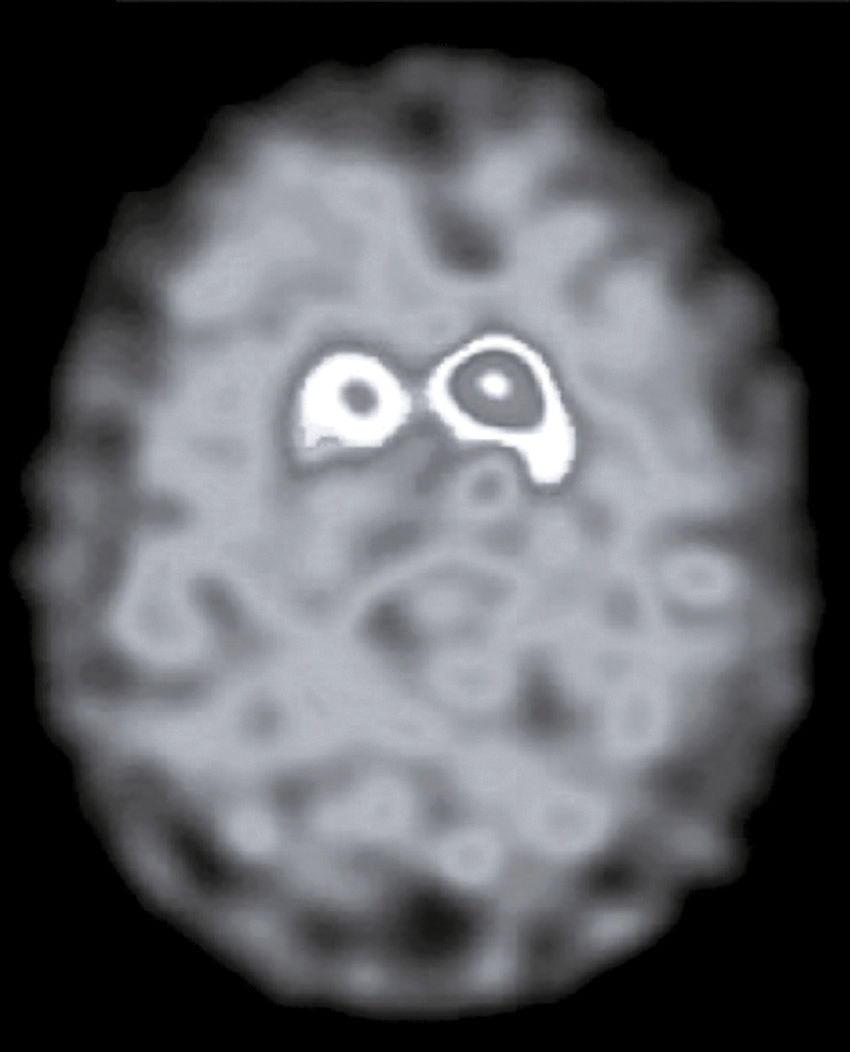

Vous débutez un traitement par benzodiazépine, vitaminothérapie B1, B6, PP, réhydratation par sérum salé et immunoglobulines polyvalentes intraveineuses associées à une héparine de bas poids moléculaire à dose isocoagulante. Le lendemain matin, le patient s’est aggravé d’un point de vue clinique. Il n’a plus d’hallucination visuelle mais il présente maintenant une tétraparésie évaluée à 3/5 avec ataxie des quatre membres, une dysarthrie, des troubles de la déglutition, et une ophtalmoplégie bilatérale. Un bilan biologique a été prélevé avant votre arrivée : numération formule sanguine : Hb : 13,8 g/dL, leucocytes : 8 600/ mm3, plaquettes : 332 000/mm3, ionogramme sanguin : Na+ : 142 mmol/L, K+ : 4,2 mmol/L, clairance de la créatininémie : 92 mL/min, glycémie : 5,8 mmol/L, transaminases, phosphatases alcalines, bilirubines et γ-GT normales, CRP : 3 mg/L.

Une IRM cérébrale a été également réalisée (fig. 31.4). Quelle est la séquence présentée ?

L'image montre une IRM (Imagerie par Résonance Magnétique) du cerveau humain en coupe axiale, c'est-à-dire une vue transversale du cerveau prise horizontalement. Cette image est particulièrement intéressante car elle permet de visualiser les structures internes du cerveau avec une grande précision. On peut observer les globes oculaires en haut de l'image, qui apparaissent comme deux cercles blancs. Les différentes zones du cerveau sont visibles, avec des variations de teintes qui indiquent les différentes densités des tissus cérébraux. La région centrale lumineuse correspond au tronc cérébral, une structure cruciale pour de nombreuses fonctions vitales. Les zones plus sombres autour du tronc cérébral représentent les hémisphères cérébraux. Cette image est utilisée pour diagnostiquer et évaluer diverses conditions neurologiques, telles que les tumeurs, les accidents vasculaires cérébraux, les infections, et les anomalies structurelles. L'IRM est une technique non invasive qui utilise des champs magnétiques et des ondes radio pour produire des images détaillées des organes et des tissus internes.

- A T1

- B écho de gradient

- C T2

- D T2/FLAIR

- E diffusion